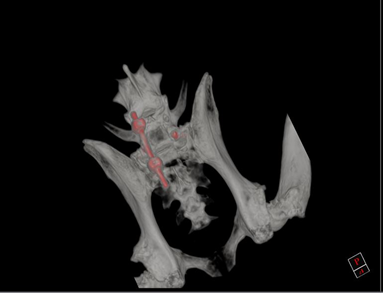

• Os